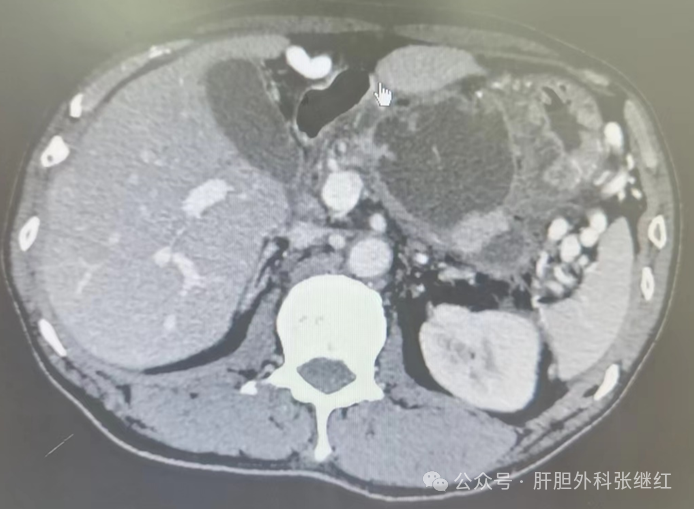

图为张继红团队腹腔镜囊肿胃吻合术前CT、手术照片和术后CT